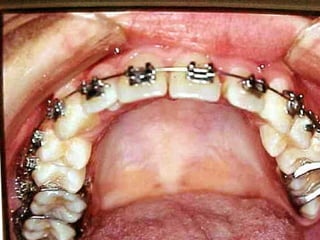

Eliminación de rotaciones.

Corrección de las discrepancias de longitud de arco.

Posición de los incisivos y molares por medio del

torque adecuado.

Llevar cualquier otra alineación en el arco.

Evita el potencial de recidiva

Aumenta la velocidad y eficacia del tratamiento

Eliminación de rotaciones. Correcciónde las discrepancias de longitud de arco. Posición de los incisivos y molares por medio del torque adecuado. Llevar cualquier otra alineación en el arco. Eliminación de rotaciones. Corrección de las discrepancias de longitud de arco. Posición de los incisivos y molares por medio del torque adecuado. Llevar cualquier otra alineación en el arco.

Evita el potencialde recidiva Aumenta la velocidad y eficacia del tratamiento